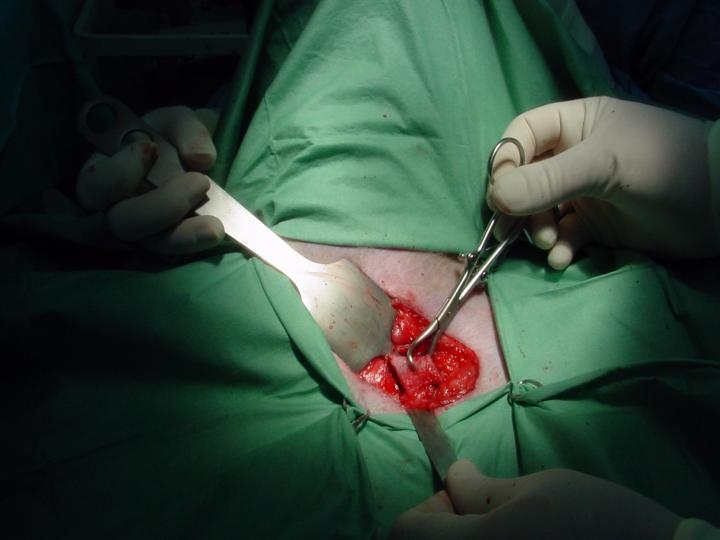

- Ostectomia do Púbis

Acesso ventral do púbis; desinserção do tendão proximal do pectÃneo.

Ostectomia de 2 cm do ramo craneal do púbis efectuada 2 mm à iminência iliopúbica.

Colocam-se afastadores de Hohman de um lado e outro para evitar lesionar o nervo obturador e a artéria e veia Circunflexas femurais.